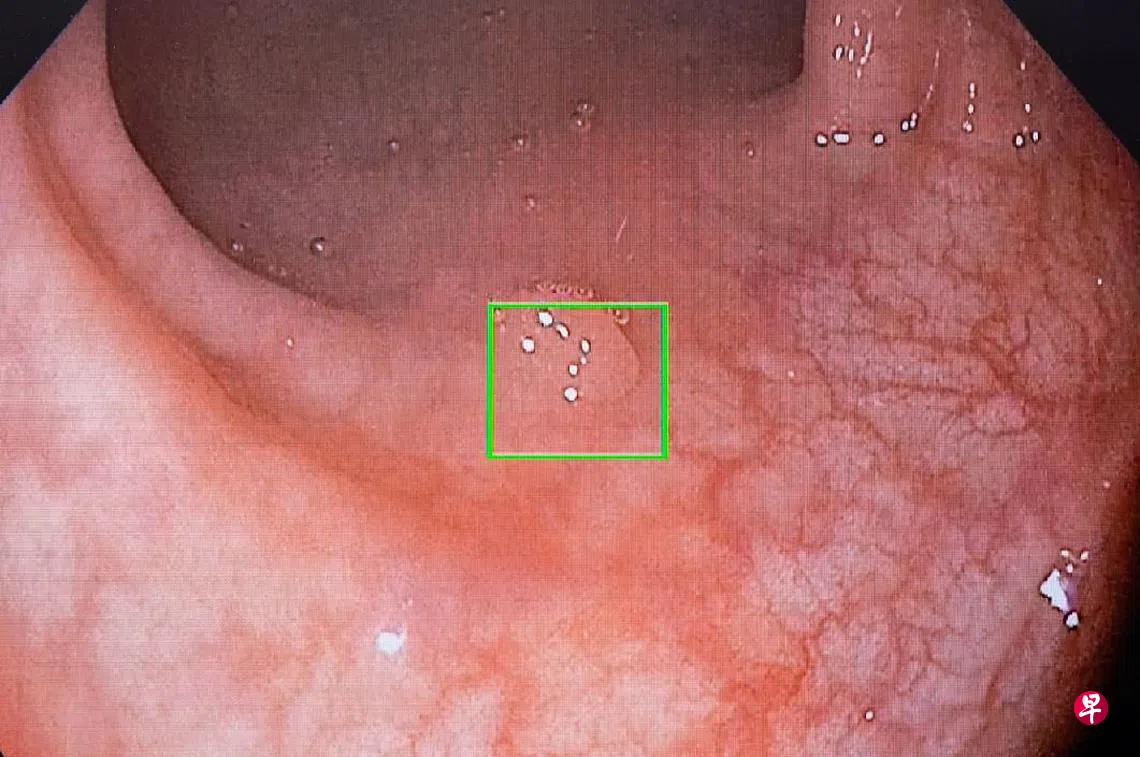

(早报讯)又小又平的息肉在大肠内虽然看起来不起眼,但随时可能发展成恶性肿瘤,引起大肠癌。尽管如此,约25%的息肉在结肠镜检查中不会被检测到。盛港综合医院采用人工智能系统,帮助医生更准确检测病患的大肠。

盛港综合医院从2021年7月开始试用美敦力的人工智能系统,一年内展开约4000起结肠镜检查。通过系统,医生在进行结肠镜检查时检测和摘取的息肉增加约6%,多数是肉眼难以辨认的息肉。系统是根据全球1300万个息肉照片进行分析和学习,随着越来越多的使用会增加检测率。